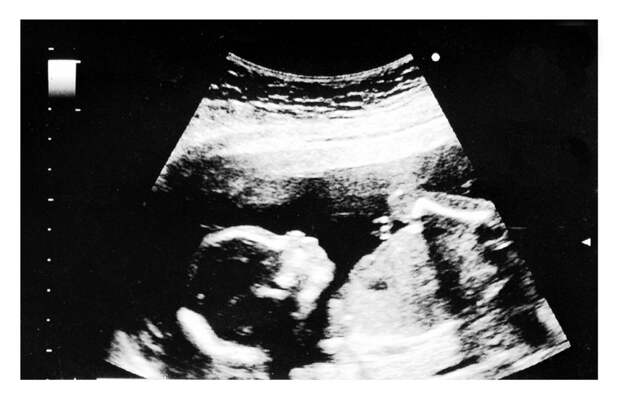

В 2010 году было отмечено, что при воздействии экстремальных температур в летний период происходит большое количество так называемых естественных абортов. Причем самоуничтожаются зародыши мужского пола. Аналогичная ситуация происходит и зимой, когда температура экстремально низкая. Ученые считают, что в экстремальных условиях мужчины менее живучи, нежели женщины.

Ученый Мисао Фукуда провел анализ детей, рожденных в Японии после землетрясений. Он изучал данные в период с 1995 по 2016 гг. И есть кое-что любопытное в его заключениях. Он заметил, что через 9 месяцев после стихийных бедствий уменьшилось число родившихся мужчин. Еще он заметил, что уровень зачатия и рождаемости снижается в зимний период. И такое повторяется ежегодно, причем мужчин становится меньше.